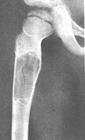

X线表现病损为界限清楚的射线透亮区,外有一薄层骨硬化边缘,由于囊肿膨胀性生长,造成骨皮质不规则变薄,X线片常呈假分叶状表现,尤多做囊肿在肱骨或股骨的干骺端向下扩展至骨干,向上扩展虽接近骨骺,但后者可被累及,病理性骨折很常见,囊肿可有骨嵴假象,病理检查见病损为单房的囊腔,其中充满清液,囊内衬以薄层纤维组织,骨折后腔内含血性液体并出现骨痂。

X线平片位于长骨干骺端,呈圆形、卵圆形或柱形,沿长骨纵轴发展,表现为轻度膨胀性生长,局部骨皮质变薄,边缘光整,无骨膜增生。合并病理骨折时,骨碎片向囊内移位,称“碎片陷落征”,有助于鉴别。

临床资料A组是待病理性骨折愈合后再治疗骨囊肿,共48例,年龄为6-43岁间;男39例,女9例。肱骨上端20例,肱骨中段6例,股骨上端9例其中(5例髋内翻),远端3例,股骨

单房性骨囊肿

颈2例,桡骨远端2例,尺骨远端1例,胫骨上端4例,腓骨头1例。B组是囊肿及骨折一并治疗,共6例,男5例,女1例。肱骨3例,股骨上端1例,股骨颈2例。

主要通过X线片及病理来诊断。X线片示,多发生于长管状骨的干骺端,髓腔中心呈圆形或卵圆形的透光区,边缘清晰而硬化,长轴与骨的长轴一致,多呈中心性生长,无骨膜反应,可见一锐利透光线横过骨病损区。病理:囊内可有少量黄色或血性稀薄液体,囊肿壁内衬一薄层纤维组织,囊内可有骨嵴分隔。镜下见囊壁由成纤维细胞多核细胞胶原纤维构成。